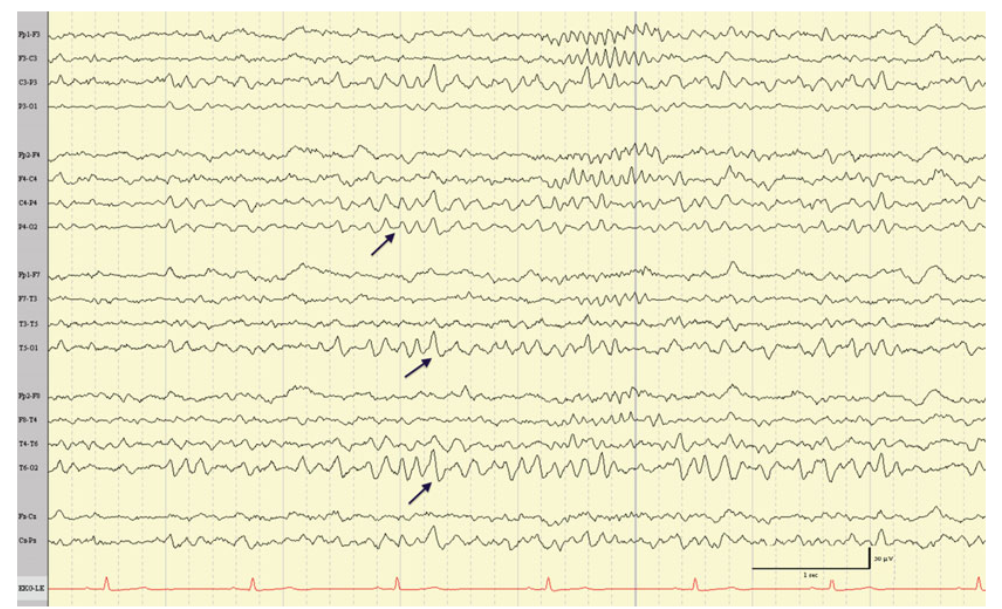

11

Q

A

Rhythmic mid-temporal theta bursts of drowsiness (RMTTBD)